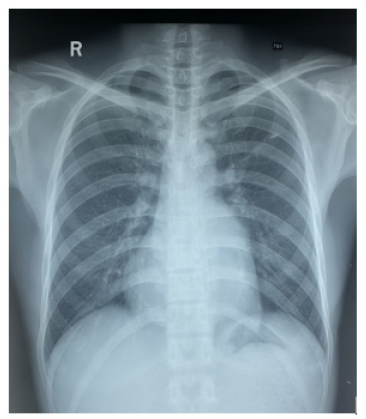

There were no features of heart failure or infective endocarditis. Figure 1 shows initial ECG on admission. ECG revealed left axis deviation with left ventricular hypertrophy. Figure 2 demonstrates Chest Xray. Heart size was upper limit of normal and lung fields were clear.